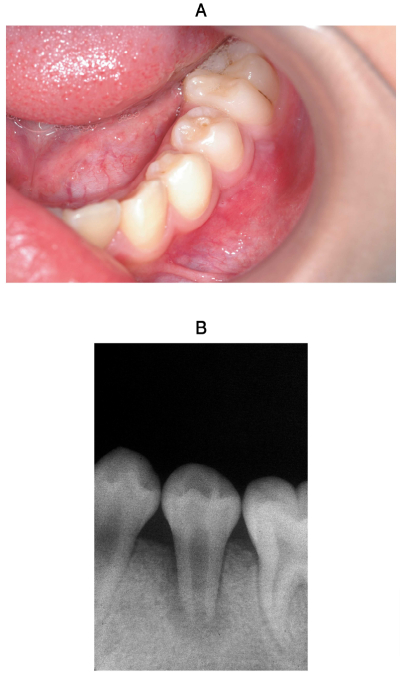

10歳の男児。下顎左側第二小臼歯の咬合痛を主訴として来院した。1か月前から同部に違和感を自覚していたが1週前から食事の際に咬合痛があるという。⎾5の動揺度は1度、自発痛はないが打診痛がある。初診時の口腔内写真とエックス線写真を示す。

適切な対応はどれか。1つ選べ。